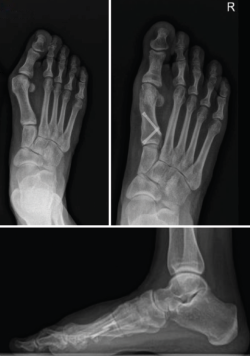

Figura 4. Caso clínico de osteotomía de apertura medial (radiología preoperatoria y control a los 6 años y 8 meses).

En las Figuras 4 y 5 se muestra un ejemplo intervenido de osteotomía de apertura y cierre.

Se han realizado 22 osteotomías proximales (15 de apertura y 7 de cierre). La puntuación de la AOFAS preoperatoria de estos pacientes era de 54, aumentando a 92 en el control realizado en el momento de la revisión (6 años y 8 meses de media); esto supone un incremento del 70%. Radiográficamente, el ángulo intermetatarsiano prequirúrgico medio era de 19° y el posquirúrgico medio era de 11,7°; por tanto, una corrección media de 7,3°. Además, ha existido un alargamiento del metatarsiano de 3 mm en las osteotomías de apertura y una disminución de 6 mm en las osteotomías de cierre (Tabla 2).